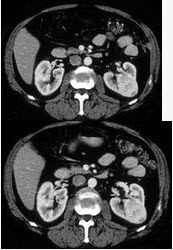

女,47岁,左侧腰部隐痛不适2个月余,结合所示图像最可能的诊断为()

A . 左肾癌

B . 左肾血管平滑肌脂肪瘤

C . 左肾出血性囊肿

D . 左肾炎性包块

E . 左肾感染性囊肿